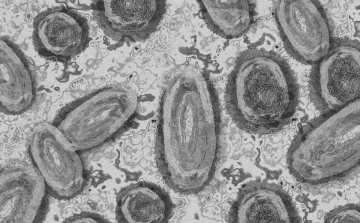

Vírusok hatástalanítására alkalmas eszközt fejlesztenek a Pécsi Tudományegyetemen

Különböző típusú vírusok hatástalanná, illetve működésképtelenné tételére fejlesztenek eszközt a Pécsi Tudományegyetem (PTE) Virológiai Nemzeti Laboratóriuma (VNL) és a RoLink Biotechnology Kft. szakemberei